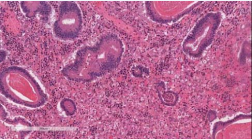

Neutrophils were especially prominent in surface ulcerated areas; vascular proliferations resembling granulation tissue developed superficially near areas of inflammation. Within the foveolar hyperplastic lining there were areas of dysplastic changes as seen in the bioptic samples, with low and high grade intraepithelial neoplasia with features of signet ring cell (Figure 2-4)

Figure 2: Hematoxylin-eosine staining.

Figure 3: Hematoxylin-eosine staining

Extensive sampling of other regions of the stomach showed atrophic, follicular, active and micro-erosive chronic gastritis of severe grade, associated to extensive type I and II intestinal metaplasia.